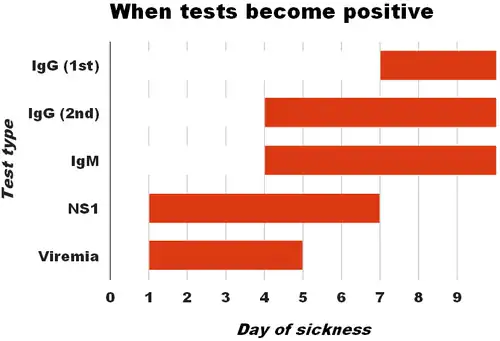

Blood tests can be used to confirm a diagnosis of dengue. During the first few days of infection, enzyme-linked immunosorbent assay (ELISA) can be used to detect the NS1 antigen; however this antigen is produced by all flaviviruses.[63][12] Four or five days into the infection, it is possible to reliably detect anti-dengue IgM antibodies, but this does not determine the serotype.[63] Nucleic acid amplification tests provide the most reliable method of diagnosis.[12]